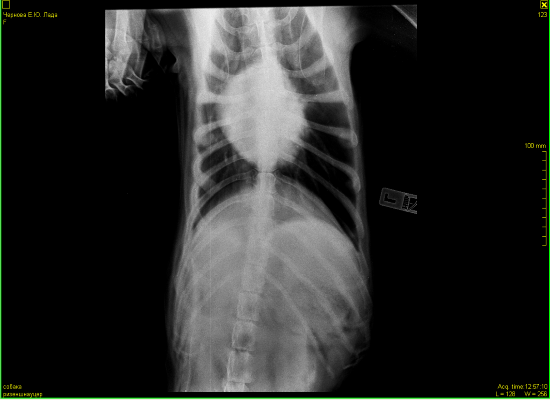

Всем доброго дня.Наши последние сводки с фронтов.В субботу мы сделали рентген.В программе,когда врач нам объяснял ситуацию,конечно было все более наглядно.Сейчас я не совсем понимаю,почему именно эти снимки открыты для доступа и почему именно их он записал.По словам врача у нас есть все ж изменения в области средостения в лимфаузлах. Что-то давит на пищевод.На снимке он должен быть прямой ,а он немного изогнут. Увеличено с одной стороны сердце и есть затемнения в легких справа(врач заметил именно затемнения,а не образования).По мне так совершенно ничего не понятно,а только больше вопросов возникло у меня.Нам назначили УЗИ и посещение кардиолога.Отсюда вопрос.Есть ли у кого ценный врач-кардиолог в районе СВАО? Операция по прежнему под ОЧЕНЬ большим вопросом.Лада пьет лекарства.Немного вялая от них.Гуляет ,кушает,спит и играет в мячик.Кашляет.

Прилагаю нашу добычу.

Катя, давить на пищевод может только опухоль ( конгломерат л/у). Эхо сердца в данной ситуации диагностически не значимая процедура(((. Надо быть очень крутым узистам, иметь экспертного класса аппарат и " удачное " расположение под лучом лимфоузлов, что бы что то разглядеть. Ведущие в диагностике средостения- КТ. Для меня косвенные признаки поражения средостения и перебронхиальной области есть(((. Для того, чтобы уменьшить перефокальное воспаление ( затемнение) и отек в л/у дала бы антибиотик, не очень забойный на 5 дней и дексаметазон - 2 укольчика с интервалом в 2- 3 дня. Теперь, что Ира скажет. Я не очень заумно? хотелось покороче и по понятней. Да, потерялась в теме, лекарства какие делаете?

В легких безусловно что то есть.... вопрос что.

Вариантов есть 2: антибиотики и повторный рентген

Или просто повторный рентген через 2 недели и сравнить.

Сердце по рентгену не увеличено, у него " сглажена талия", что может быть при перегрузке правого сердца, которое отвечает за легкие . Повышено внутрилегочное давление из за mts в лимфоузлах скорее всего корня легких. Возможно начинает скапливаться жидкость в перекарде, а может все вместе. Мы никак не сможем на все это повлиять. Для всего, что я описала нужно не просто увидите жидкость в перекарде, а померить давление на лёгочной артерии, доплер на узи аппарате нужен. В принципе, что хотели узнать - есть там что то или артефакт. Есть(((. Грядку оперировать? Считаю, что операция только усугубит страдания. Все таки я за антибиотик и дексаметазон, и посмотреть. Клинически может уменьшиться кашель.